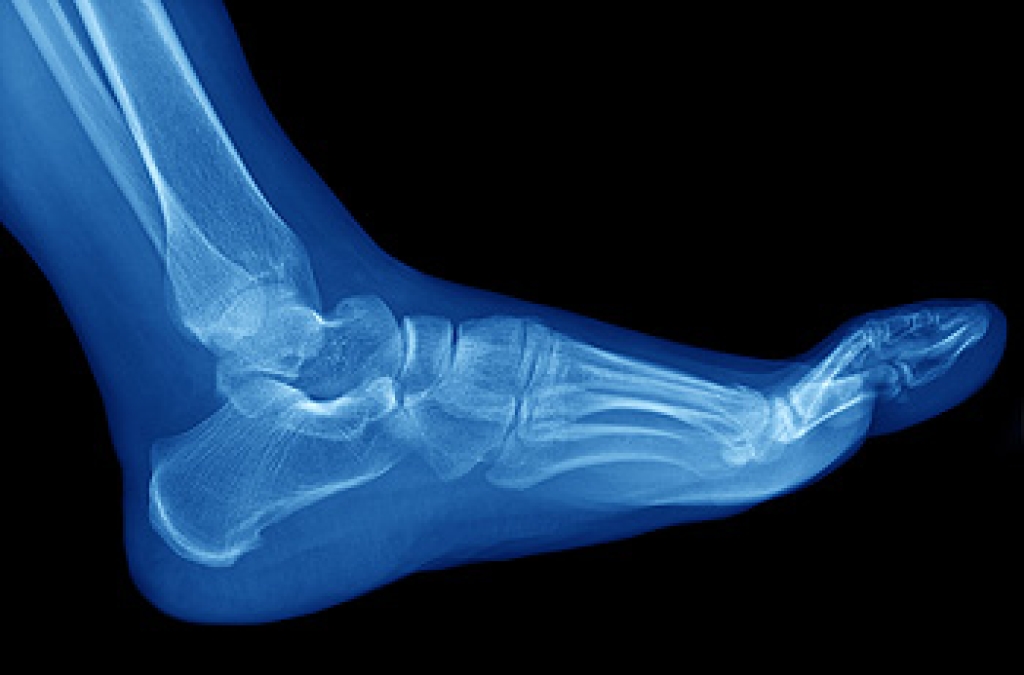

One of the functions of the feet is providing mobility and supporting the weight of the body. The feet are considered to be one of the most complex structures in the body, and are constructed of 26 bones, several muscles, tendons, and ligaments. There are numerous foot conditions which can develop from enduring an injury, or from wearing shoes that do not fit correctly. There are several types of bones that are found in each foot. These are referred to as the phalanges, which are the bones in the toes, and the metatarsals that are found within the flat part of the foot. All the foot bones work in synchronized harmony, and most people are unaware until there is foot pain. An injury can occur to parts of the foot other than the bones. A ligament is defined as a strong tissue that connects the bones together. An injured ligament may require a longer recovery time as a result of limited blood flow. If you would like to have additional knowledge about how the feet are constructed, it is suggested that you consult with a podiatrist who can provide you with the information you are seeking.